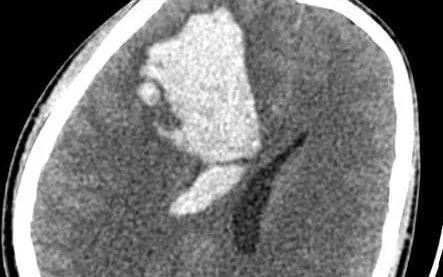

Tại Bệnh viện Đa khoa Bắc Ninh số 2, kết quả chụp cắt lớp vi tính cho thấy bệnh nhân bị xuất huyết não nặng, tình trạng đe dọa trực tiếp đến tính mạng. Ngay lập tức, các bác sĩ tiến hành phẫu thuật và xử trí cấp cứu. Nhờ được can thiệp kịp thời, người bệnh đã hồi phục rõ rệt chỉ sau vài ngày điều trị.